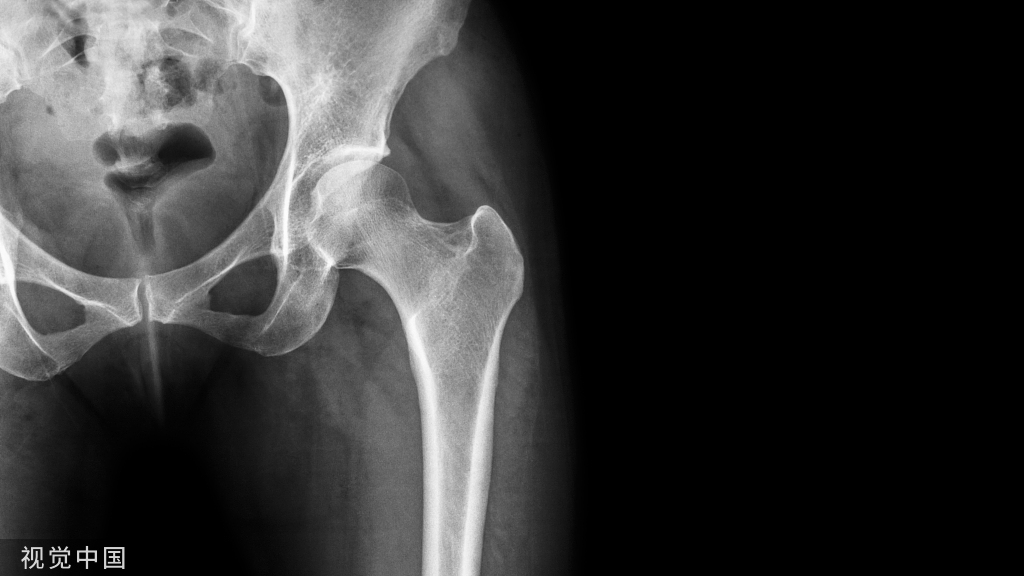

Wallis动态稳定系统生物力学的主要研究方面是邻近椎体活动度(ROM)和应力传导。KOROVESSIS等通过对该系统术后60个月随访发现,Wallis棘突间内植物控制非融合椎体邻近椎体ROM,恢复了该节段的DH,但是减少了整个腰椎前凸和矢状平衡。JIANG等使用第2代Wallis动态稳定系统,在张力的作用下固定并限制椎间活动幅度,卸载椎间盘和关节突关节上的压力,保持腰椎稳定,对邻近节段退变(ASD)具有延缓作用。生物力学测试显示,植入物增加了手术节段150%的硬度,限制了35%的活动度,这两项研究均表明可以认为这是植入物的负面影响。LAFAGE等分析Wallis棘突间内植物可使椎间盘和纤维环的应力减少,这可能会缓解疼痛。众多研究表明Wallis动态稳定系统的弹性系数与正常脊柱相似,在生物力学上不仅恢复了病变节段的DH,而且卸载椎间盘和关节突关节上的压力,对ASD具有延缓作用。但众多研究也有矛盾之处,Wallis动态稳定系统是否具有以上作用,还需进一步研究。